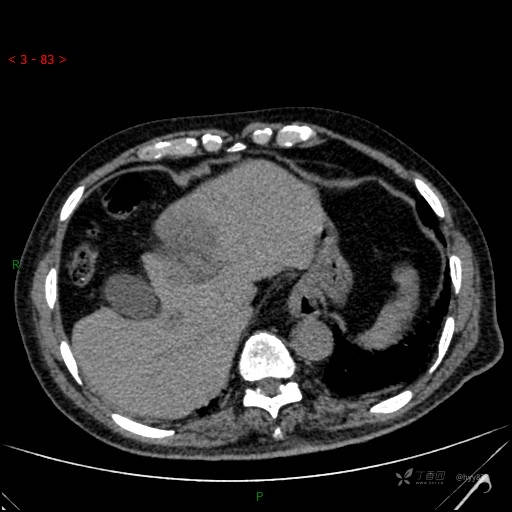

增强动脉期

img